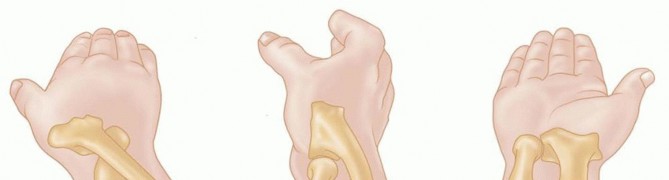

Open Reduction and Internal Fixation of Radial Head and Neck Fractures